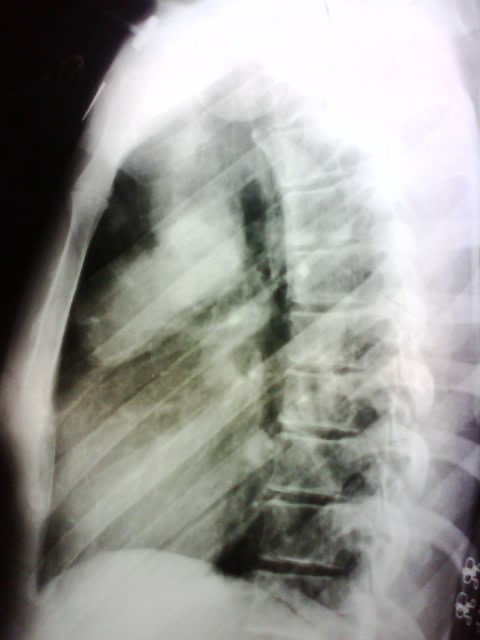

标题: X4932:女,22岁.体检发现.请各位分析可能是什么. [打印本页]

标题: X4932:女,22岁.体检发现.请各位分析可能是什么.

右肺上叶前段病变,临床资料太少,不好定。建议查血象、ct进一步检查。

右肺上叶前段病变,因是体检发现,估计没有临床症状,考虑良性占位,不除外结核。

考虑右肺上叶良性肿块;建议行进一步检查。

结核?动静脉畸形??进一步检查吧

病灶位于上叶前段,不是结核好发部位,不过患者较年轻,又是体检才发现的,考虑结核可能性大,但单就一平片,很难做出最后更有说服力的结论,所以还是建议ct